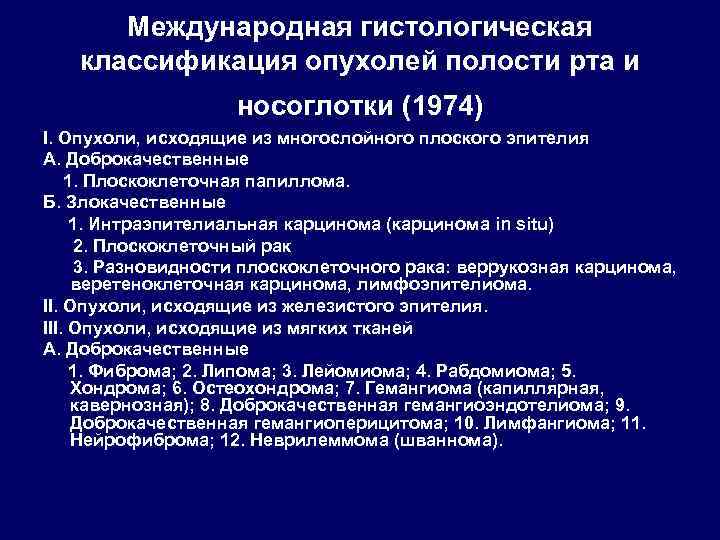

Международная гистологическая классификация опухолей полости рта и носоглотки (1974) I. Опухоли, исходящие из многослойного плоского эпителия А. Доброкачественные 1. Плоскоклеточная папиллома. Б. Злокачественные 1. Интраэпителиальная карцинома (карцинома in situ) 2. Плоскоклеточный рак 3. Разновидности плоскоклеточного рака: веррукозная карцинома, веретеноклеточная карцинома, лимфоэпителиома. II. Опухоли, исходящие из железистого эпителия. III. Опухоли, исходящие из мягких тканей А. Доброкачественные 1. Фиброма; 2. Липома; 3. Лейомиома; 4. Рабдомиома; 5. Хондрома; 6. Остеохондрома; 7. Гемангиома (капиллярная, кавернозная); 8. Доброкачественная гемангиоэндотелиома; 9. Доброкачественная гемангиоперицитома; 10. Лимфангиома; 11. Нейрофиброма; 12. Неврилеммома (шваннома).

Международная гистологическая классификация опухолей полости рта и носоглотки (1974) I. Опухоли, исходящие из многослойного плоского эпителия А. Доброкачественные 1. Плоскоклеточная папиллома. Б. Злокачественные 1. Интраэпителиальная карцинома (карцинома in situ) 2. Плоскоклеточный рак 3. Разновидности плоскоклеточного рака: веррукозная карцинома, веретеноклеточная карцинома, лимфоэпителиома. II. Опухоли, исходящие из железистого эпителия. III. Опухоли, исходящие из мягких тканей А. Доброкачественные 1. Фиброма; 2. Липома; 3. Лейомиома; 4. Рабдомиома; 5. Хондрома; 6. Остеохондрома; 7. Гемангиома (капиллярная, кавернозная); 8. Доброкачественная гемангиоэндотелиома; 9. Доброкачественная гемангиоперицитома; 10. Лимфангиома; 11. Нейрофиброма; 12. Неврилеммома (шваннома).